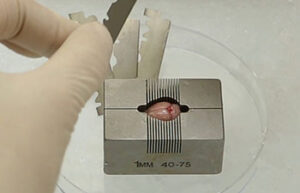

- Surgery and biopsy

- Mice and rat brain edema test

- Mice and rat brain TTC test